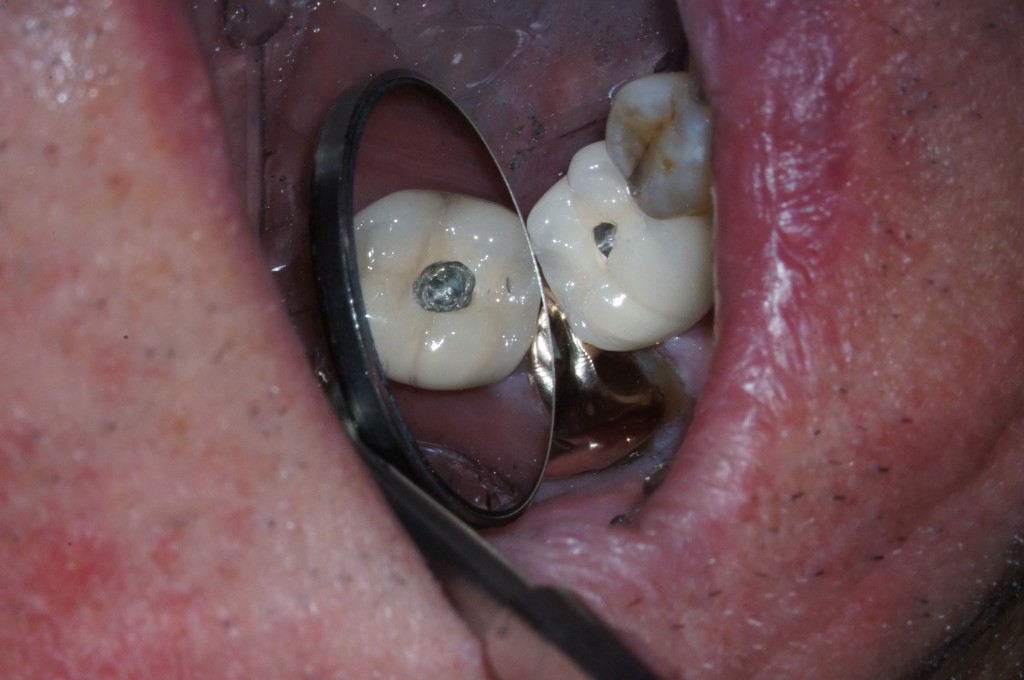

While you could try to tap the crown off the abutment, you are faced with two potential problems – breaking the abutment screw and damaging the internal threads of the implant. Due to this risk, I prefer to access the abutment screw though the crown leaving an access hole similar to an endodontic access. It’s worth noting if the crown is rotating on the implant, it can help you determine the location of the screw since it should be in the center of the point of rotation. It is important to remember that while you may place material such as cotton, wax or Teflon over the abutment screws, a previous dentist may not have used those materials.

When it comes to trying to find the screw my best advice is to make sure you aren’t pushing it too far. You do not want to damage the screw; this could complicate removing the screw, or worse, you could damage the implant itself. While you and your patient will be disappointed if you cannot save the crown, it will be much worse if you damage the implant and possibly lose the implant itself.

Even if you can’t safely locate the screw, you still have to get the restoration off, so the question now becomes “What now?” In cases like this, I like to cut the mesial and distal of the crown off to create a diastema on both sides that is large enough to allow you to rotate the crown to remove it. Of course the downside to this approach is the fact that the restoration is now ruined and the patient will need a new one. While we prefer to avoid this, it is far better than compromising the implant itself.